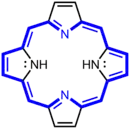

Porphyrin-based sensitizers

Porphyrin-based sensitizers, initially used as a photosensitizer in PDT, are fairly hydrophobic molecules derived from hematoporphyrin.[1] Single oxygen atoms or hydroxyl radicals are produced by porphyrin-based sensitizers upon exposure to ultrasound or light, providing the cytotoxic effects desired with sonodynamic and photodynamic therapies.[1] However, the result of porphyrin-based sensitizers is not as local as desired for sonodynamic therapy since they are also located in non-targeted tissue between the tumor and the ultrasound emitter.[1]